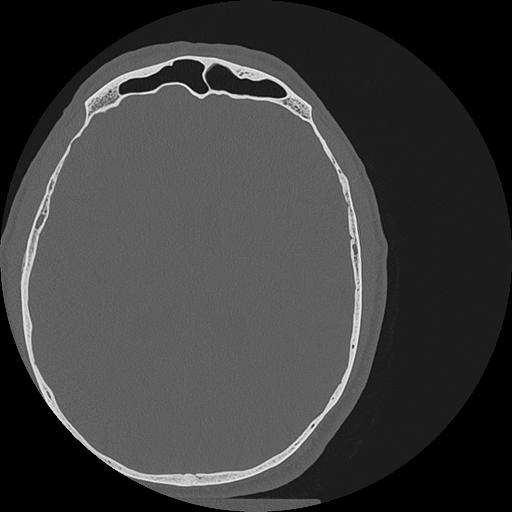

7 HUESO,,Vol,0.5,HUESO,,